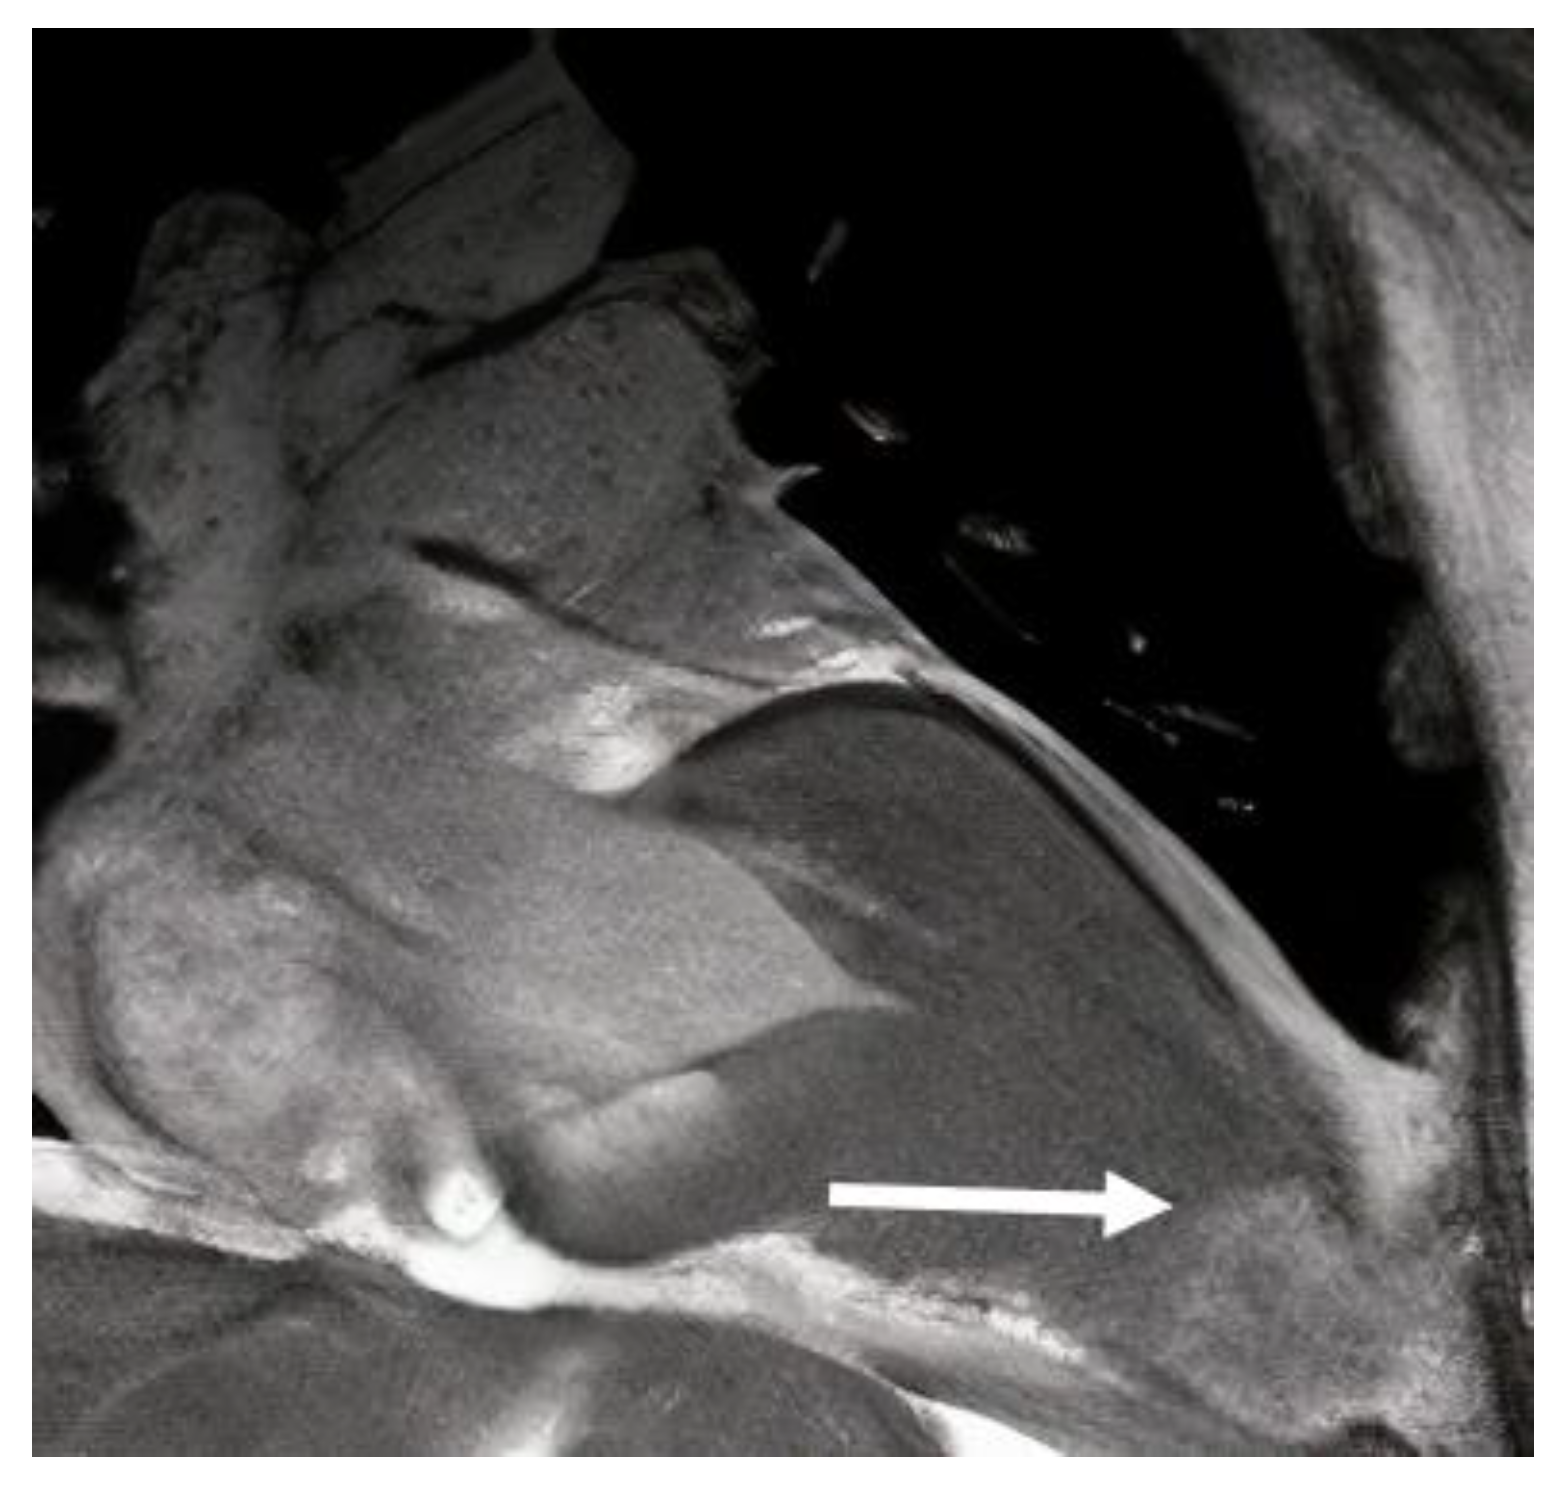

- Moon, J.C.; Fisher, N.G.; McKenna, W.J.; Pennell, D.J. Detection of apical hypertrophic cardiomyopathy by cardiovascular magnetic resonance in patients with non-diagnostic echocardiography. Heart 2004, 90, 645–649. [Google Scholar] [CrossRef]